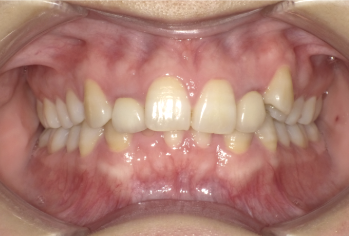

過蓋咬合軽度症例画像

軽度(下の前歯が少し隠れる程度)の方の場合

下の前歯が上の前歯にやや隠れている状態で、見た目の気になり方が強くなく、噛みにくさや顎の痛みなどの自覚症状も少ない場合、ワイヤー矯正やマウスピース型矯正装置のどちらでも対応しやすく、前歯の重なりを浅くし、奥歯の高さを少し整えることで改善を目指します。治療期間はおおよそ1年前後が目安となります。